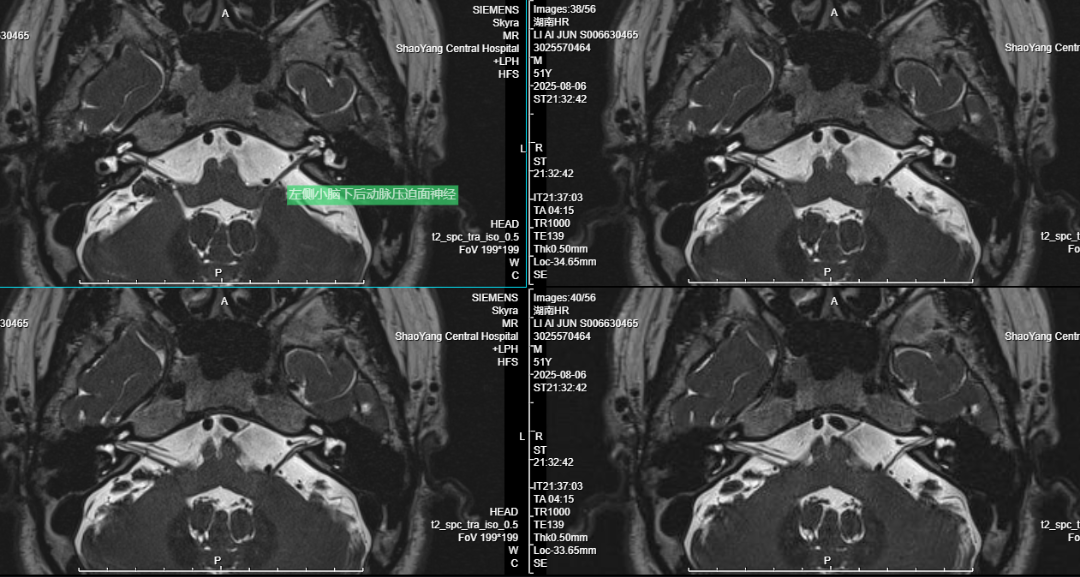

患者李某某,因“左眼睑不自主抽动9个月,加重2个月”入院。术前MRI检查明确血管神经压迫关系。经充分术前评估,神经外科团队为其施行“左侧面神经微血管减压术”。

图片 2.png

如果出现一侧面部不自主抽搐,应尽早前往神经外科或神经内科就诊。早期诊断和干预可避免症状加重和心理负担。MRI 3D-TOF序列成像可辅助明确诊断,微血管减压术是有效的治疗选择。